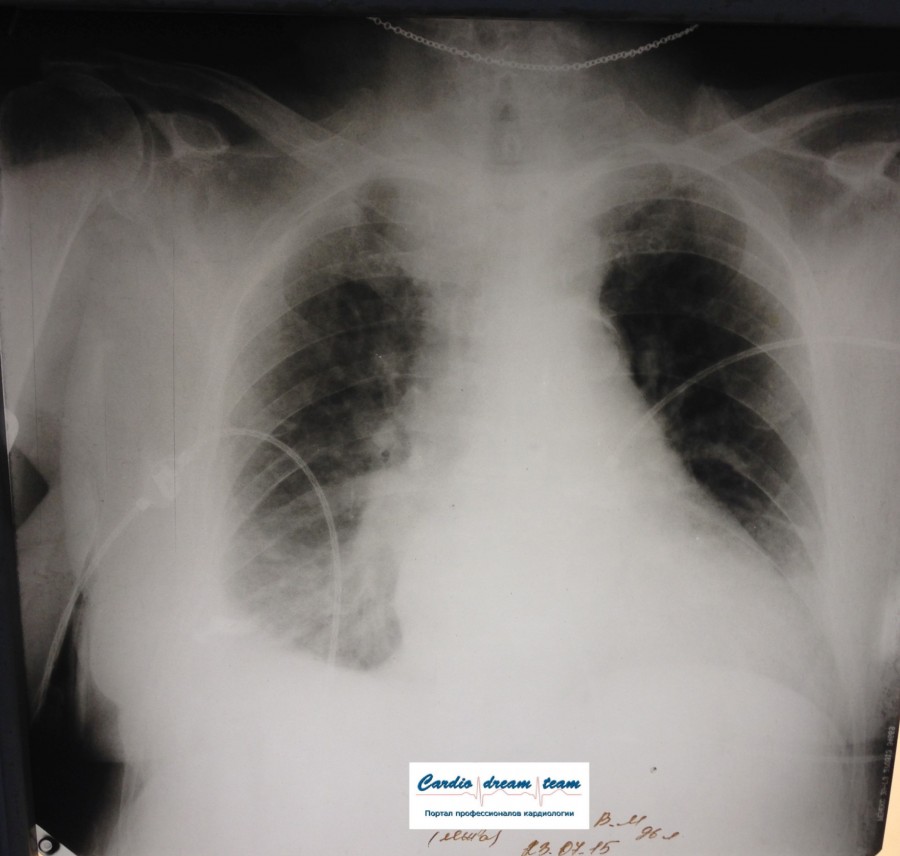

Не обсуждалась Дата 23-ИЮЛ-15 ОПИСАНИЕ: Проведена рентгенография органов грудной клетки в прямой проекции, положение лежа, условия ПИТ Легочные поля: неравномерно прозрачны за счет сосудистого обогащения, в базальных отделах с обеих сторон, отмечается сгущение легочного рисунка, за счет гиповентиляции, в плевральных полостях жидкость Легочный рисунок: Изменен по смешанному типу: обогащен за счет сосудистого компонента, деформирован за счет склероза. Корни: бесструктурны, расширены за счет сосудистого компонента, обогащены Синусы: определяется наличие жидкости по линии 5 ребра Сердце: широко лежит на диафрагме отмечается расширение границ сердечной тени влево, вправо экг-электроды. ЗАКЛЮЧЕНИЕ: Рентген-признаки 2-х стороннего гидроторакса с гиповентиляцией базальных сегментов.. Признаки застоя по МКК 2 степени (умеренно выраженный). Пневмосклероз. Р-признаки гипертрофии левого желудочка сердца. Склероз аорты.

IMG_4339--.jpg [ 717.06 KiB | Просмотров: 29303 ]